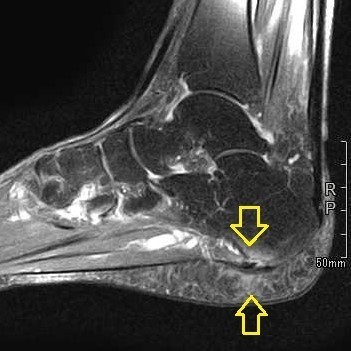

当院では、診察時にレントゲンと超音波検査、MRI等を用いて痛みの原因組織を特定し、それらに合った適切な治療を提案しています。足底腱膜炎では超音波で足底腱膜の肥厚やMRIで足底腱膜・脂肪体・踵骨の信号変化などを確認し、診断しています。これら画像所見の異常は変性(微細損傷)が起こっていることを示しており、また異常な神経線維の増殖によって痛みに対して過敏になっていることも考えられます。それらに対する有効性が報告されています。①短期的な除痛効果

インソールの作成とリハビリを行い痛みは軽減してきていたが、趣味の再開とともに痛みが再発したため、MRI検査を実施。

画像所見から体外衝撃波の適応症例と考え、本人の希望もあり施行しました。

足底腱膜・踵骨骨髄(⇩)・脂肪体(⇧)が白くなっています。これが変性部です。